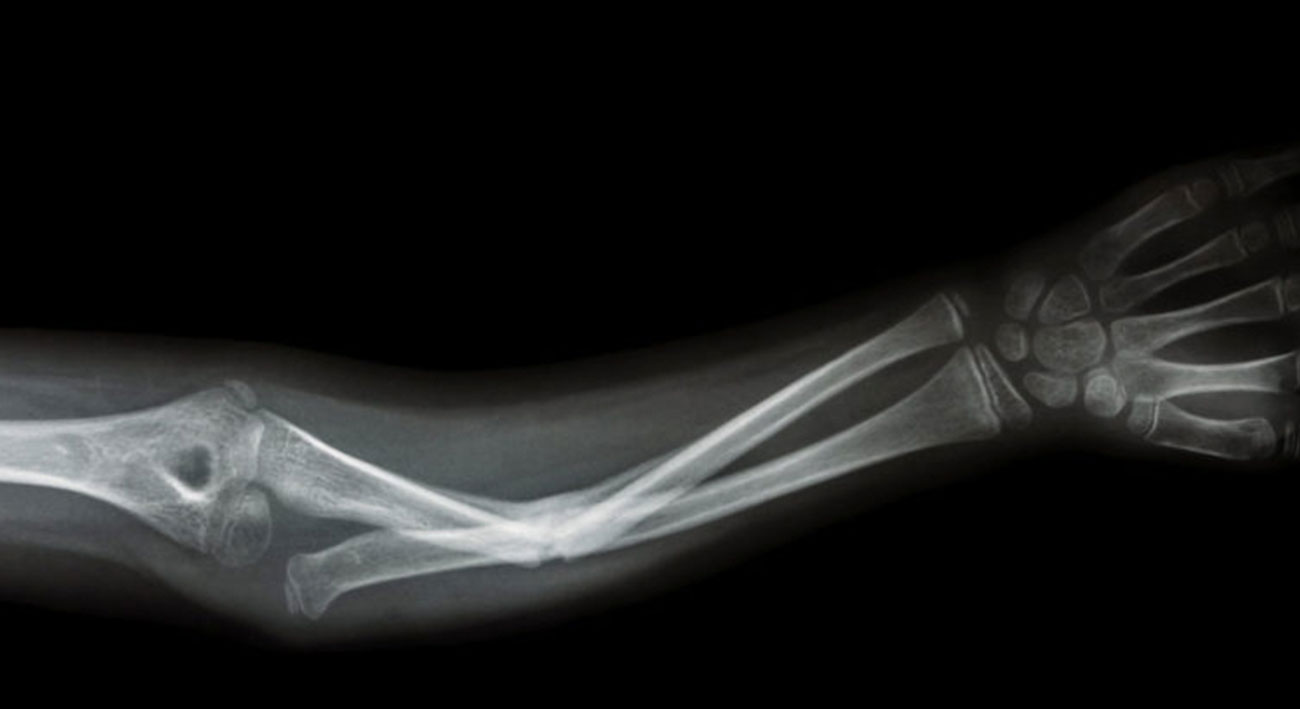

Краеугольный камень традиционной ортопедической медицины всегда заключался в том, чтобы обездвижить переломанные кости и позволить телу восстановиться. К счастью, наши тела прекрасно справляются с ремонтом костей; при правильной подгонке и достаточном времени, кости могут залечить даже очень серьезный урон, станут почти такими же хорошими, как новые.

Современные методы физическое терапии и методов восстановления улучшили этот подход «зафиксируй и забудь», добавив к нему активность, диету и покой, чтобы получить наилучшие результаты после сращения сломанных костей. Особо травматические случаи могут потребовать хирургических операций — установки штифтов, пластин и других конструкций, которые потребуют более продолжительного времени восстановления, большего объема физиотерапии, да и боли будет, откровенно говоря, больше. Возможности для улучшения процедур имеются в целом, но только в самых крайних случаях.